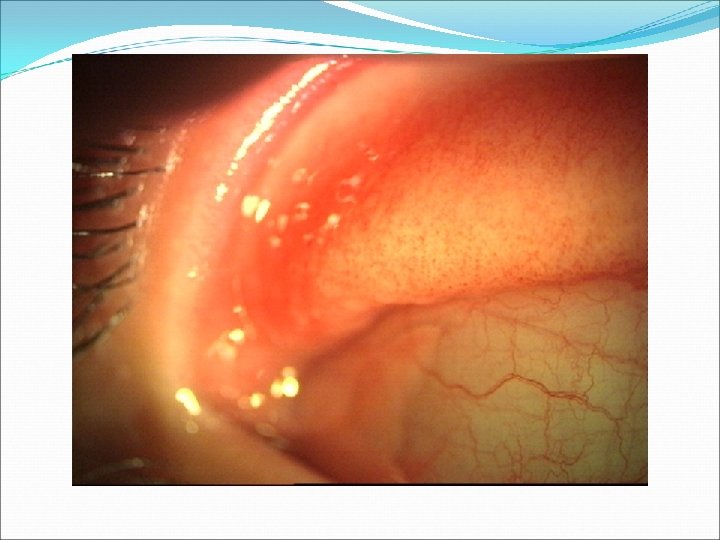

PAPİLLER REAKSİYON Kronik Blefarit Allerjik Konjonktivit Bakteriyel Konjonktivit Kontakt lens kullanımı Superior Limbik Keratokonjonktivit

VERNAL KONJONKTİVİT Kapak tipi Limbal tip